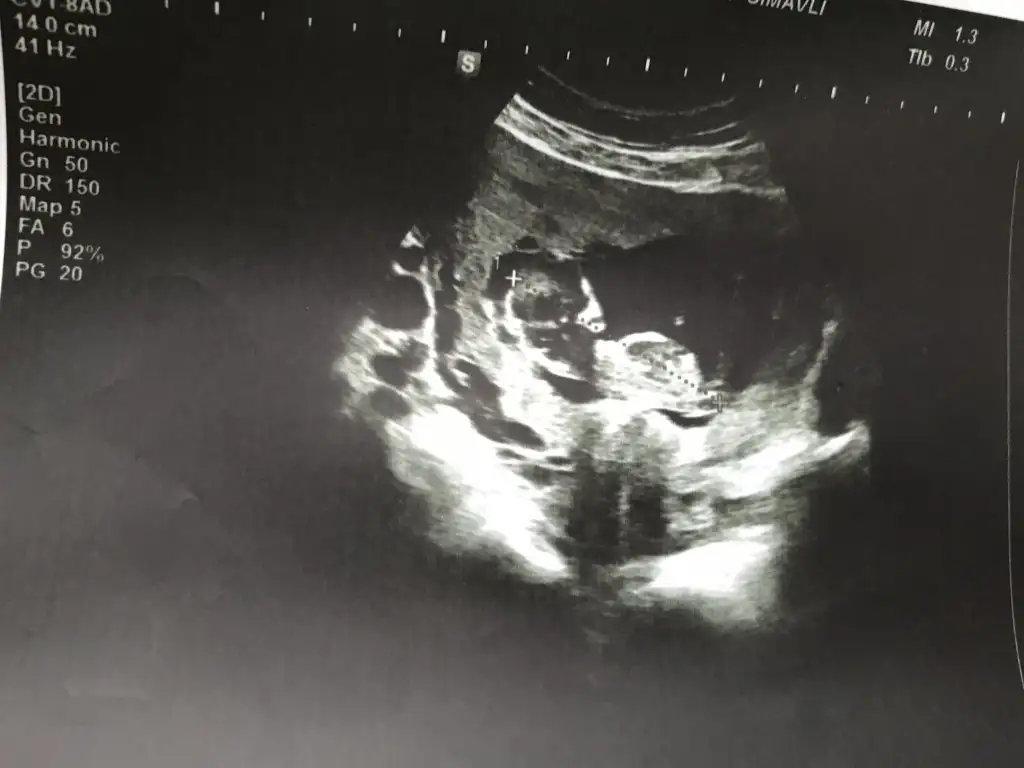

dr soylemeden siz gorun genital nub teorisi ( bebegin cinsiyeti)

Banada yorum yapabilcek varmı 12+2 yiz